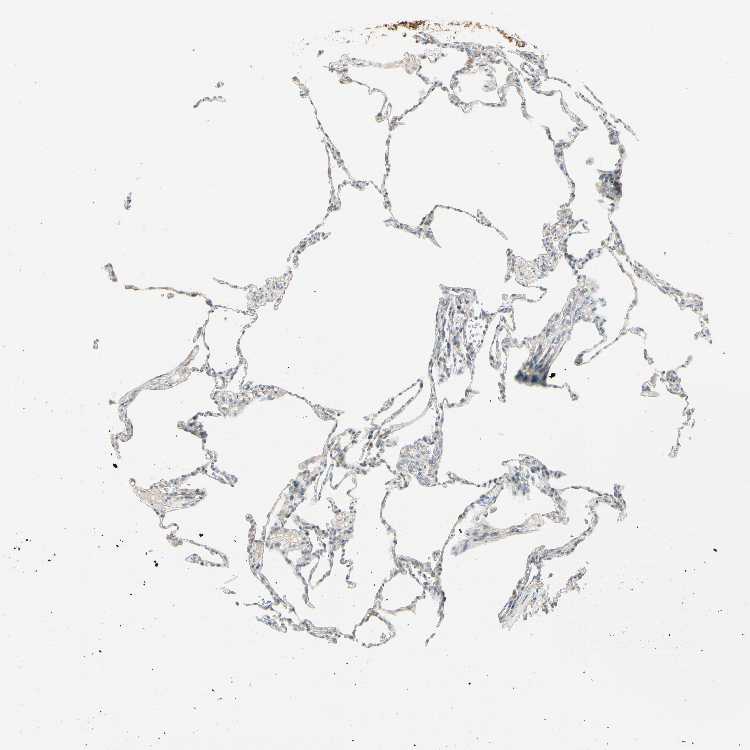

Antibody staining in the annotated cell types in the current human tissue is reported as not detected, low, medium, or high. This score is based on the staining intensity and fraction of stained cells.

Information about each individual sample is listed below, including gender, age, a tissue section image and estimated fractions of cell types. pTPM (transcripts per million) values give a quantification of the gene abundance which is comparable between different genes and samples.